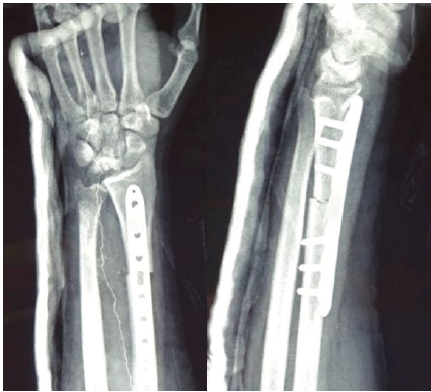

A representative example of Case 1 is illustrated in Figures 1–6. The preoperative radiograph is shown in Figure 1, while Figure 2 demonstrates the MRI findings confirming avascular necrosis of the lunate. Figures 3–5 depict the immediate postoperative radiographs and sequential follow-up images up to 1 year. Figure 6 shows the final clinical photograph, demonstrating a good functional outcome.

Figure 3: This shows the post-operative image in anteroposterior and lateral, showing radial shortening osteotomy with fixation with a 3.5 mm LCDCP plate for stability. It shows radial height maintained and ulnar variance corrected, putting less load on the lunate.